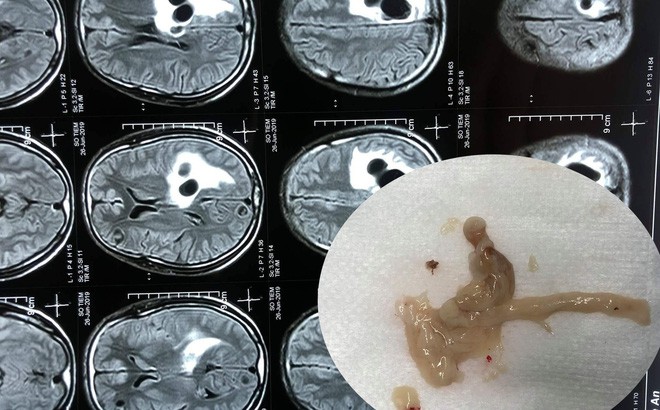

04/07/2019 21:52Đau đầu đi cấp cứu phát hiện 5 ổ sán lớn nằm trong não người đàn ông ăn tiết canh

Ngày 3/7, Bệnh viện hữu nghị đa khoa Nghệ An cho biết, bệnh viện này vừa phẫu thuật vét 5 ổ sán trong đầu một bệnh nhân nam do ăn tiết canh, ăn đồ sống.

Qua thăm khám và chụp CT não cho thấy có 5 ổ sán nằm rải rác trong não bệnh nhân S.. Trong đó có một ổ sán lớn trên đỉnh của bệnh nhân gây phù não. Bệnh nhân sau đó được chỉ định can thiệp ngoại khoa để lấy được trọn vẹn ổ nang sán khỏi não.

Ca mổ thành công, bệnh nhân S. hồi phục, tỉnh táo, không liệt, đi lại và sinh hoạt bình thường.

Các bác sỹ tại bệnh viện cho biết, kén sán não là bệnh nhiễm trùng hệ thần kinh do ấu trùng sán sống ký sinh ở người gây ra. Bệnh thường gặp ở người dân ăn thịt lợn chưa nấu chín, ăn tiết canh, ăn gỏi sống.